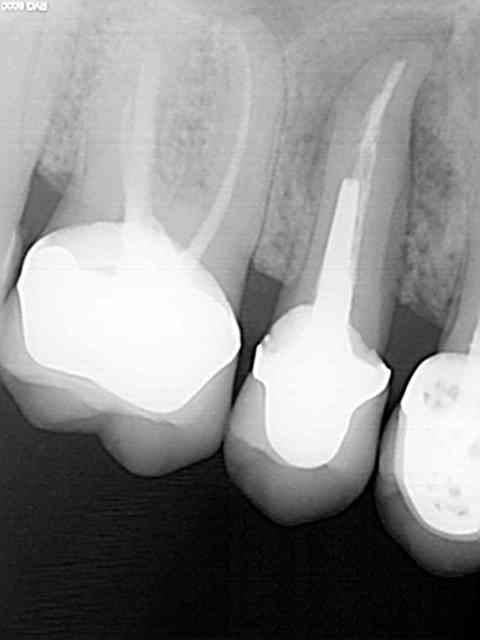

Comme promis, je donne des nouvelles de mes débuts avec le Legacy 3.

1er implant avec ce système, ce matin.

Remplacement, d'une 15 fracturée. Dent extraite en décembre 2011, attente de la cicatrisation à cause de l'infection importante autour de la dent et pose aujourd'hui d'un 3.7 longueur 10.

Quelques radios pour illustrer le cas...

Js 1 wjplje - Eugenol

Js 2 vpryz9 - Eugenol

Js 3 orny9q - Eugenol